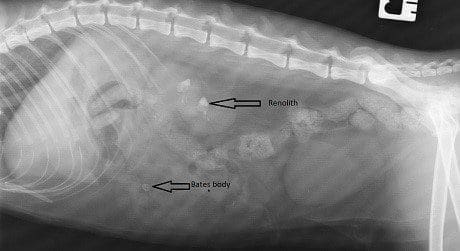

Lateral and DV abdominal radiographs were obtained which confirmed that Lucy has fairly sizeable bilateral renoliths (Figure 2). It would seem likely that these are calcium oxalate given previous history and presence of hypercalcaemia. A Bates body which is thought to occur due to fat necrosis was also noted incidentally.

Figure 2. A right lateral abdominal radiograph. Radiopaque renoliths are visible within the collecting system of both kidneys (red arrows). The incidental fat necrosis appears as a round radiopaque area within the ventral abdomen (yellow arrow).